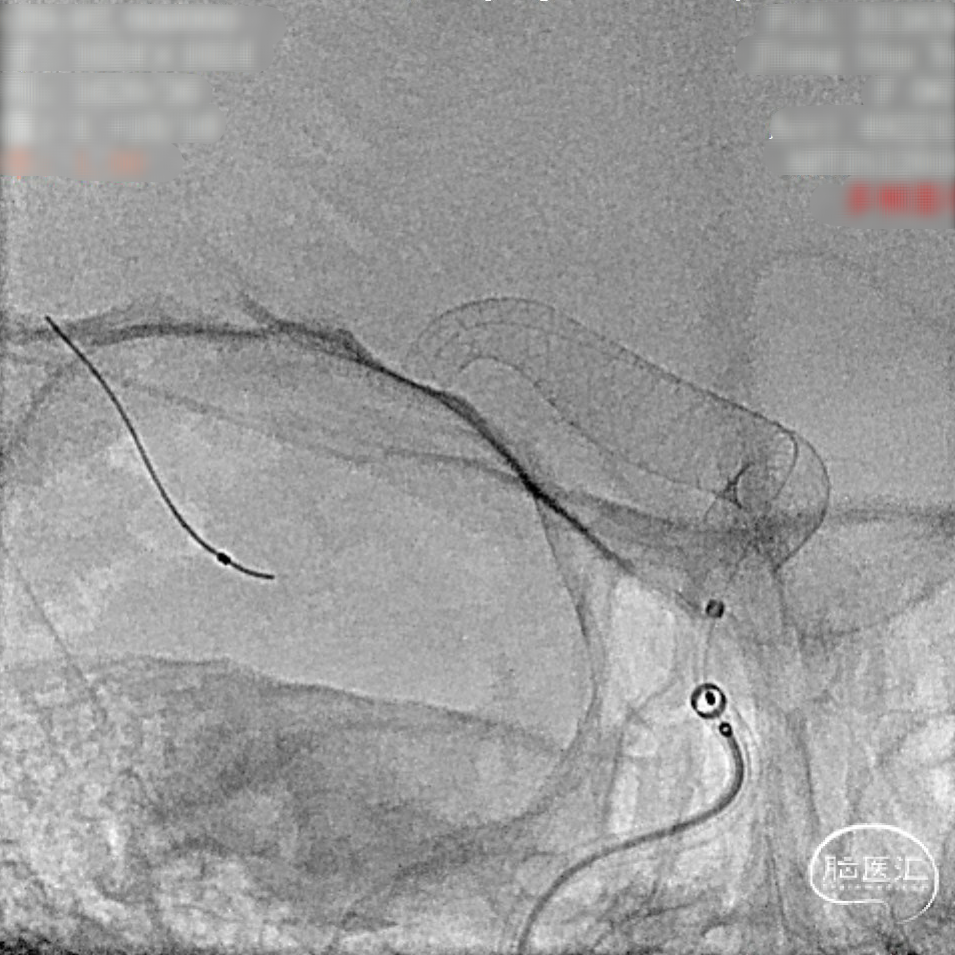

微导管到位后释放支架头端。

头端完全打开,锚定。

完全覆盖动脉瘤颈后拟过弯。

支架完全释放。

造影明确打开贴壁满意。